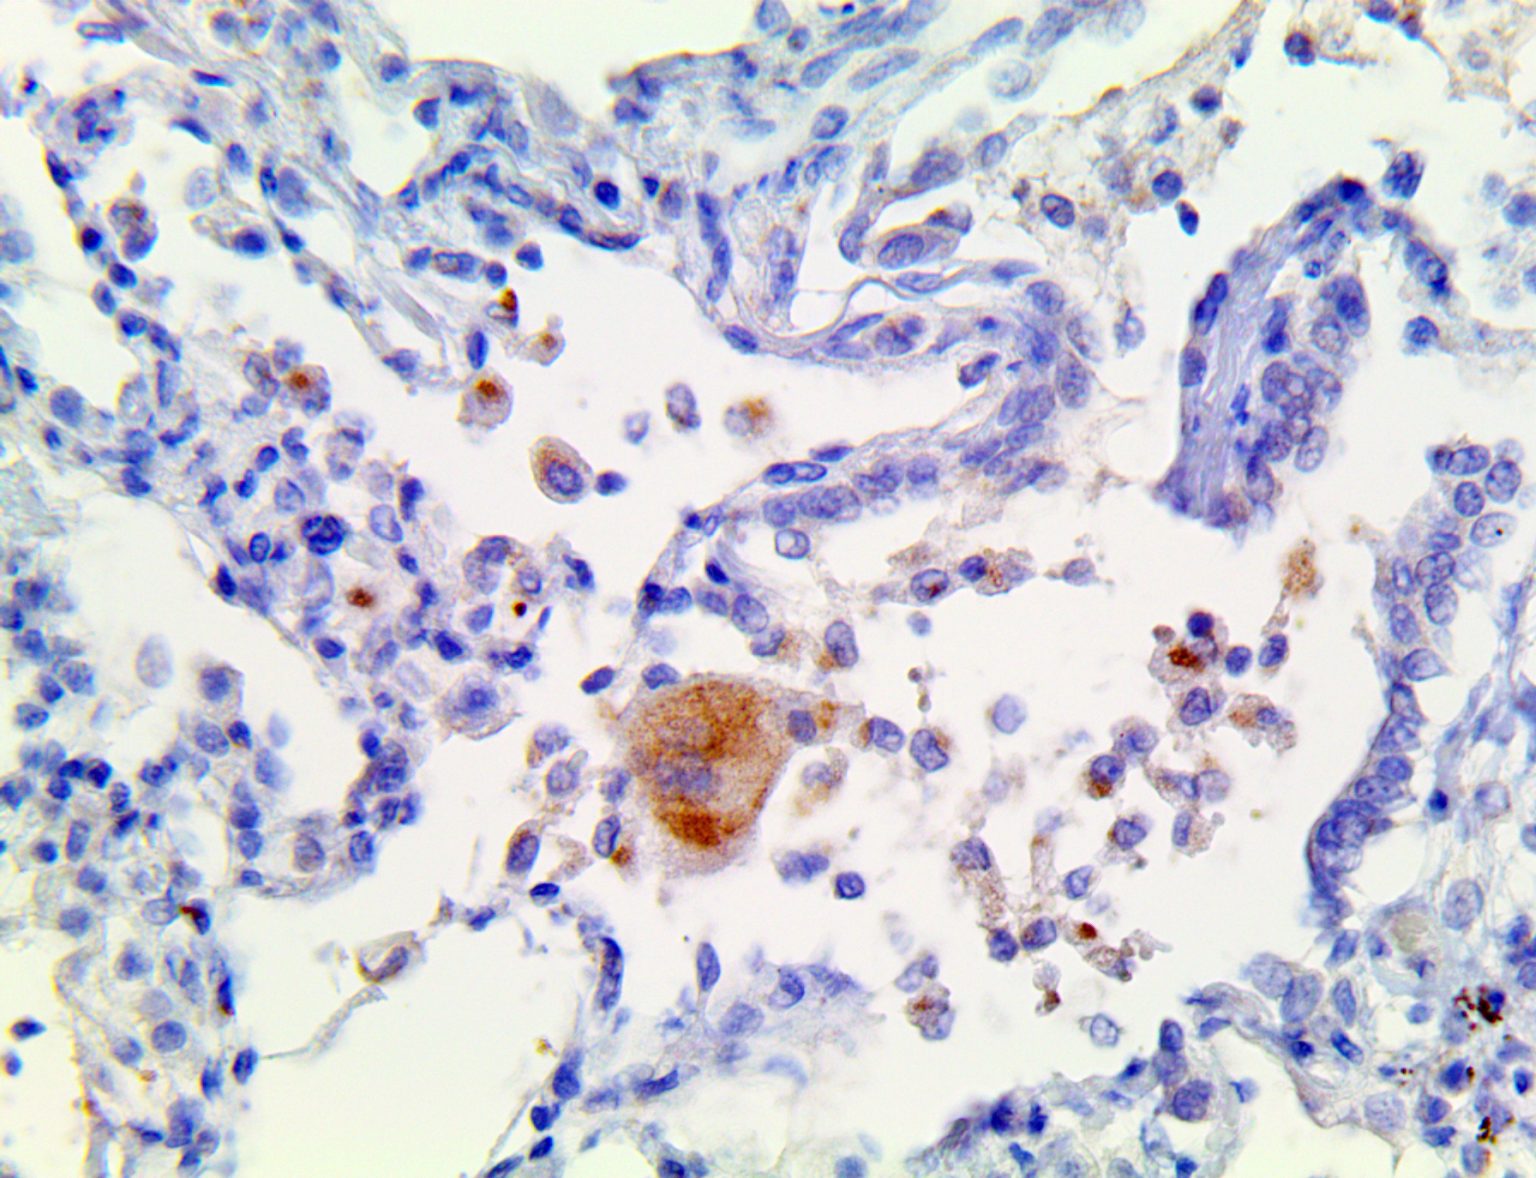

It is the ICU physician who is most likely to witness one of the deadliest manifestations of the abnormal immunological response, the cytokine storm syndrome (CSS). This response is also referred to by some as the cytokine release syndrome (CRS). CSS is characterized by continuous activation and expansion of macrophage and lymphocyte populations, which secrete large amounts of cytokines, causing the cytokine storm. This massive cytokine release is akin to hemophagocytic lymphohistiocytosis (HLH) disease, a syndrome characterized by initial unchecked and persistent activation of cytotoxic T lymphocytes and NK cells.

Clinical and laboratory manifestations of HLH include fever, enlarged liver and/or spleen, neurologic dysfunction, coagulopathy, liver dysfunction, cytopenias (i.e., low levels of erythrocytes, leukocytes, and/or platelets), hypertriglyceridemia, hyperferritinemia, hemophagocytosis, and eventually diminished NK cell activity as the immune system becomes progressively paralyzed. HLH can be familial (primary HLH) or secondary to another disease process (sHLH), such as rheumatic disease, in which it is referred to as macrophage activation syndrome (MAS, characterized by elevated ferritin).

This activation induces inflammatory monocytes to highly express IL-6, starting a localized and then systemic cascade effect that results in hyperproduction of IL-6, which accelerates the inflammatory process. Because IL-6 also increases vascular permeability, excessive levels cause blood vessels to become very leaky. This, along with clotting factors released from vascular endothelial cells, stimulates the coagulation cascade, resulting in microthrombosis (tiny clots), which leads to ischemia and tissue death of the kidney, intestines, heart, liver, brain and extremities.